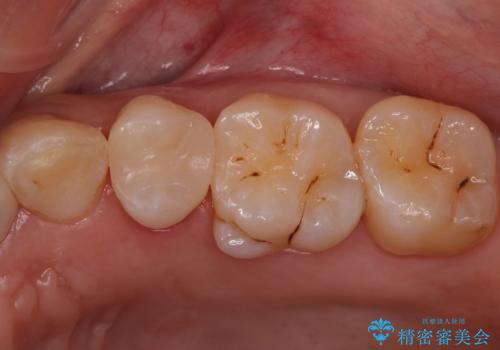

銀の詰め物を白くしたい セラミックインレーでの治療

- 銀歯が気になるためやり替えたいとのことで来院されました。

セラミックインレーで治療を行いました。

- 左上5 セラミックインレー 77,000円費用は治療当時の料金となります